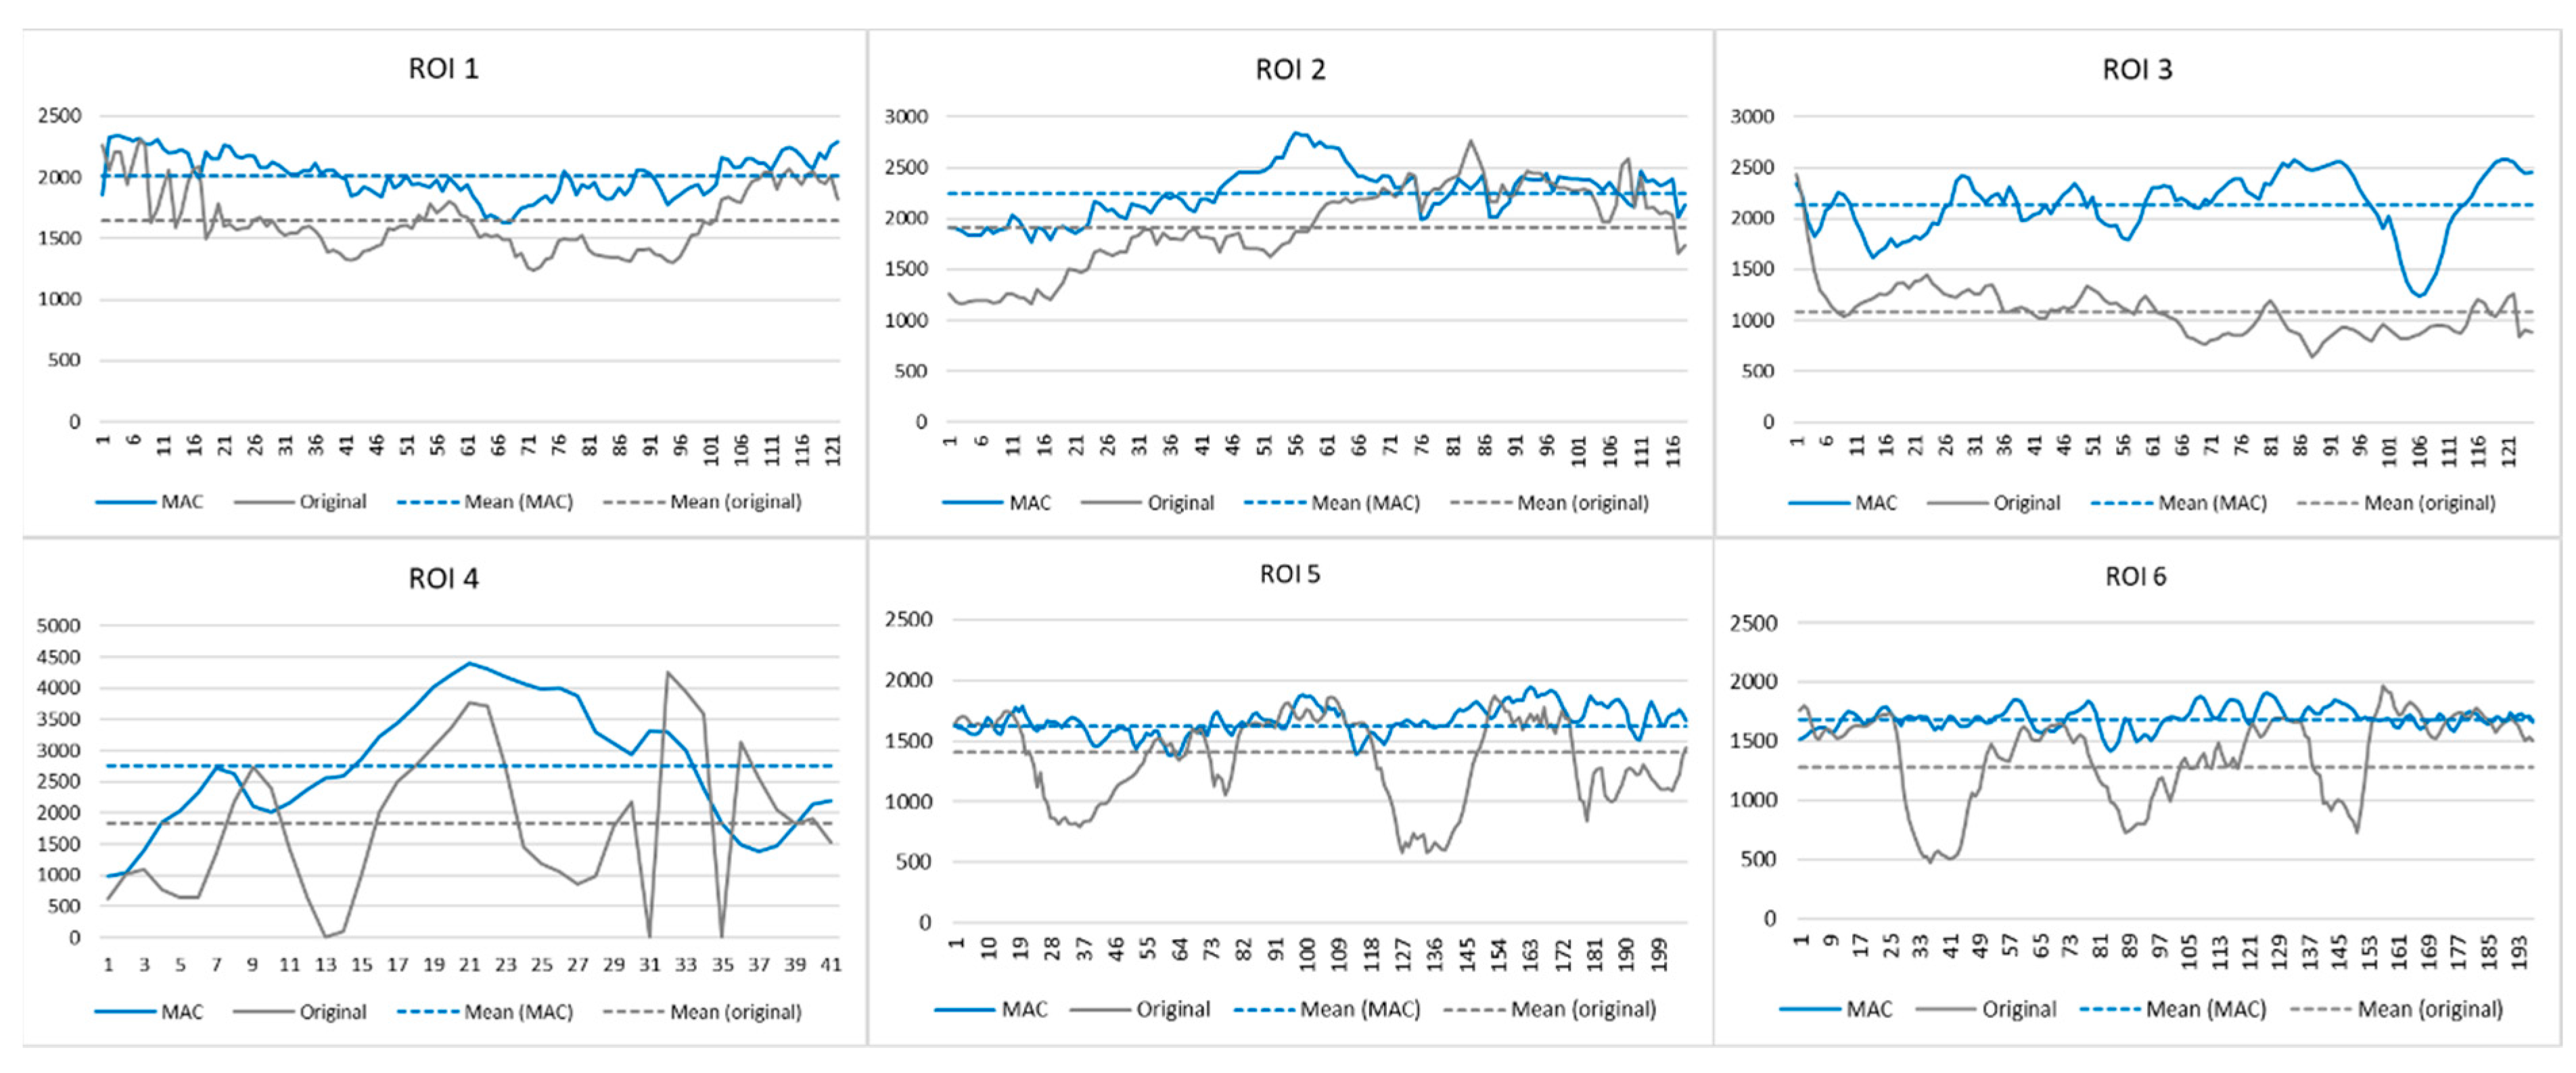

2.4. Experiment 2

2.5. Experiment 3

3. Results